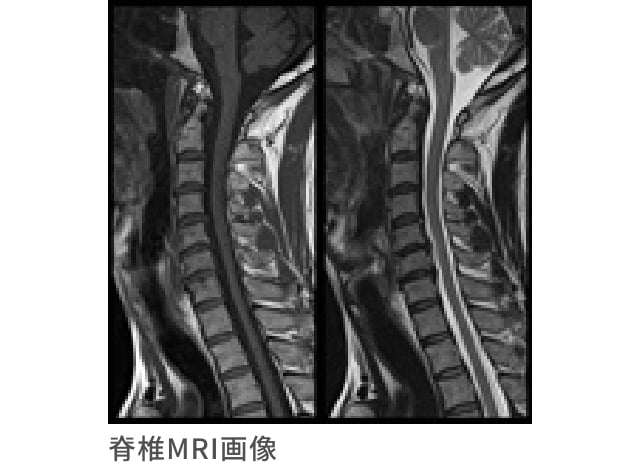

脊椎MRI検査

首・肩・背中・腰の痛みや手足の痺れなどの原因となる椎間板ヘルニアをはじめとする脊椎疾患の早期発見に有効な検査です

現代病ともいわれる慢性的な肩こりや腰痛―その原因は運動不足、長時間のデスクワーク、スマートフォンの普及など様々ですが、代表的な疾患として椎間板ヘルニアなどの脊椎疾患が挙げられます。

頚椎は7個、胸椎は12個・腰椎は5個の骨から形成され、その間を直結しクッションの役割をするのが椎間板です。椎間板ヘルニアは、椎間板の一部分が突出し神経を圧迫することで痛みや痺れの症状が現れます。

MRI検査では、この突出した箇所を鮮明に写し出すことが可能であり、神経のどの部分が圧迫されているのかを診断することができます。また、その他にも様々な脊椎の疾患を早期に発見できる有用な検査です。